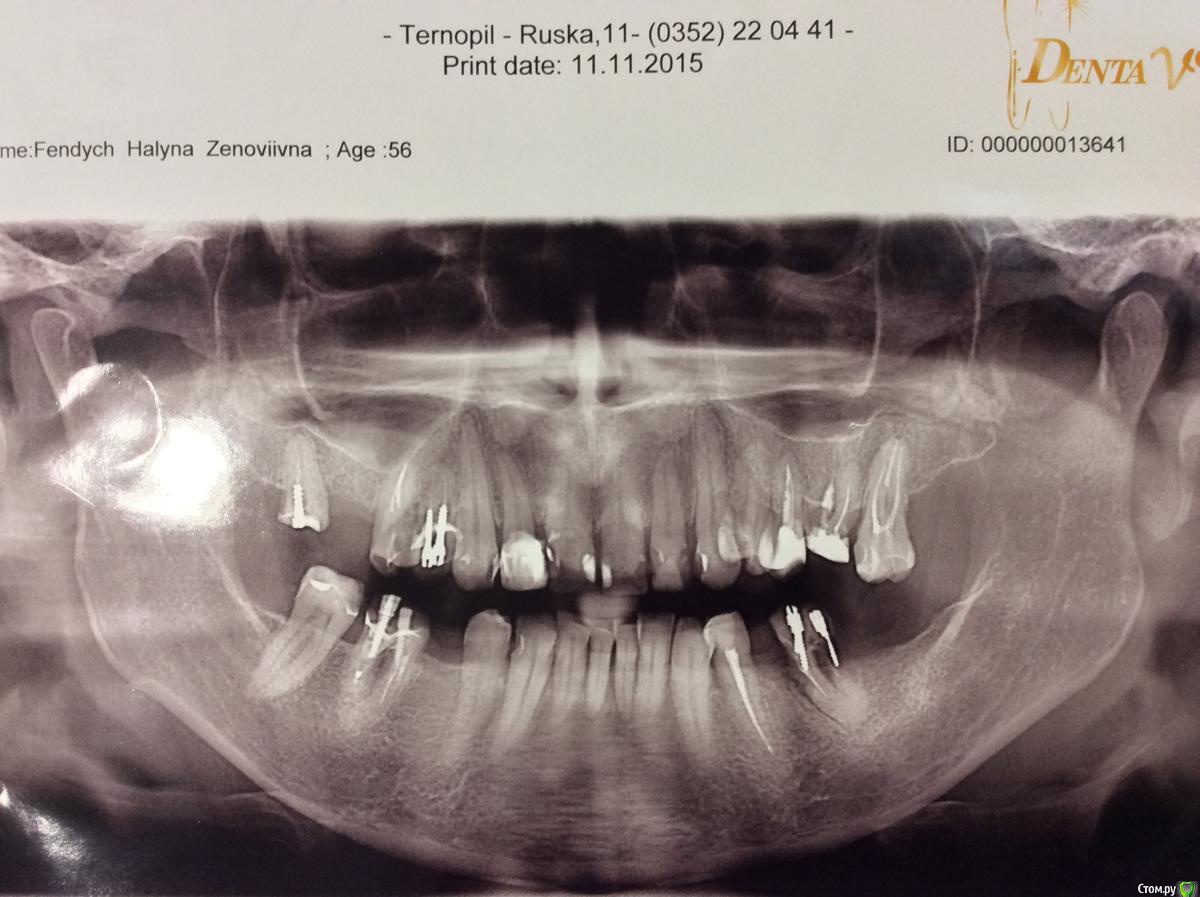

dr.Dre Опубликовано 22 сентября, 2016 Поделиться Опубликовано 22 сентября, 2016 (изменено) Добрый вечер коллеги,прошу вашего совета как протезировать? Изменено 22 сентября, 2016 пользователем dr.Dre Ссылка на комментарий

Карен Аванесов Опубликовано 23 сентября, 2016 Поделиться Опубликовано 23 сентября, 2016 (изменено) Костя шутник и балагур. Но тему лучше не засорять флудом, все очень серьезно, поможем коллеге реальным советом. Вижу долгое и мучительное лечение у ортодонта, затем не менее мучительную хирургию два синуса на чистом ауто, латерализацию н.н., ламинаты по Кури. Тотальную депульпацию и.... в завершении венец стоматологии коронацию. Изменено 23 сентября, 2016 пользователем Карен Аванесов Ссылка на комментарий